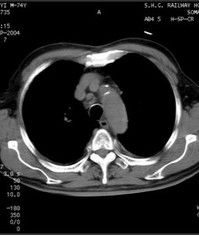

5.肺部病變。肺門和氣管周圍淋巴結腫大,肺野可見粟粒樣結節或網點狀陰影。肉芽腫滿布於肺泡內時雙肺可呈絮狀陰影。偶有咳嗽和胸痛症狀。